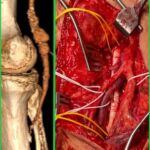

Περιφερική αγγειοπάθεια

Η περιφερική αγγειοπάθεια είναι η νόσος κατά την οποία οι αρτηρίες που τροφοδοτούν τα άκρα στενεύουν ή αποφράσσονται, συνήθως λόγω αθηροσκλήρωσης, μειώνοντας τη ροή αίματος προς τους ιστούς.